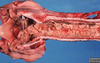

Pathogenesis (img)

Grain overload, rumenal acidosis, mucosal damage, opportunistic fungal infection, vasculitis, ischemia and mucosal ulceration